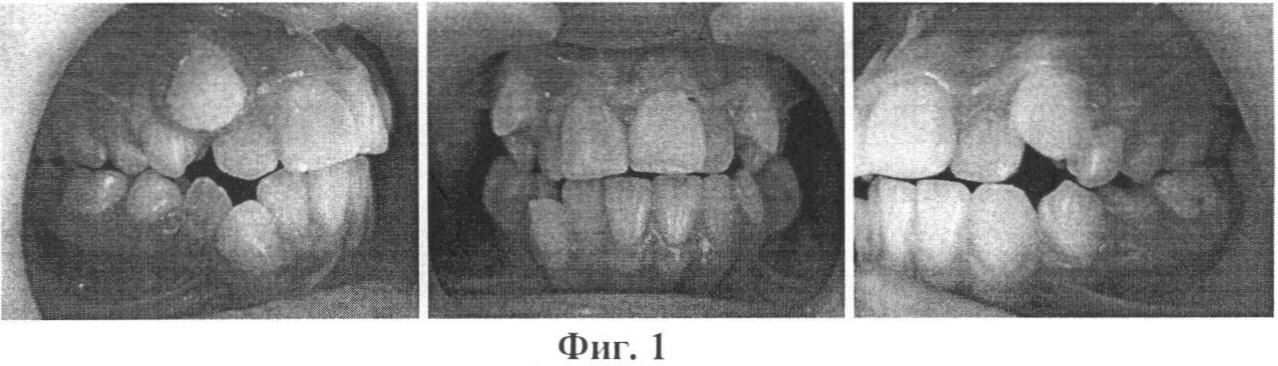

Изобретение иллюстрируется фотографиями, где на фиг.1 и 2 показаны зубные ряды верхней и нижней челюстей пациентки А., на фиг.3 – расположение несъемного аппарата с тремя направляющими на верхней челюсти для расширения и удлинения верхнего зубного ряда (стрелками указано направление активации винта), на фиг.4 показана реплантация клыка и премоляра, фиксация брекетов на эти зубы, шинирование в зубном ряду при помощи ортодонтической дуги и металлических лигатур, разобщение прикуса за счет окклюзионных накладок из стеклоиономерного цемента на 36 и 46 зубы, на фиг.5 показаны фотографии зубных рядов пациентки А. после ортодонтического лечения, на фиг.6 показана фиксация брекетов, колец и небного бюгеля на зубы верхней челюсти, на фиг.7 – зубные ряды пациентки А. верхней и нижней челюстей после ортодонтического лечения, на фиг.8 – ортопантомограмма пациентки А. до ортодонтического лечения, на фиг.9 – ортопантомограмма пациентки А. через 6 месяцев после реплантации клыка и премоляра, на фиг.10 – ортопантомограмма пациентки А. после ортодонтического лечения, на фиг.11 – телерентгенограммы пациентки А. до и после ортодонтического лечения, на фиг.12 и 13 – гипсовые модели пациентки А. до и после ортодонтического лечения соответственно.

Клинический пример. Пациентка А., 12 лет 6 мес., (история болезни 9100018802) обратилась в детскую поликлинику с жалобами на некрасивую улыбку, выступание вперед верхних клыков, наличие двух клыков на нижней челюсти справа, один из которых развернут на 180°, отсутствие клыка на нижней челюсти слева (фиг.1).

На основе клинических и дополнительных методов исследования был поставлен диагноз: нейтроокклюзия, сужение и укорочение верхнего зубного ряда, вестибулярное положение 13, 23, 43 зубов; дефицит места в зубном ряду; адентия 44, транспозиция 33 (на месте 44), разворот по оси на 180°; небное положение 12, 22 зубов; тесное положение резцов на верхней и нижней челюсти I и II степени.